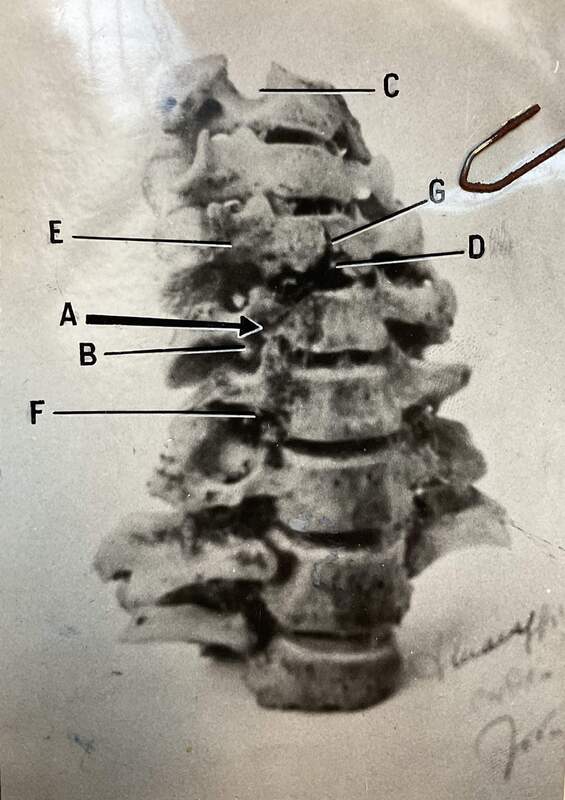

Le vertebre di Vincenzina Virando con l'indicazione dei segni dei proiettili